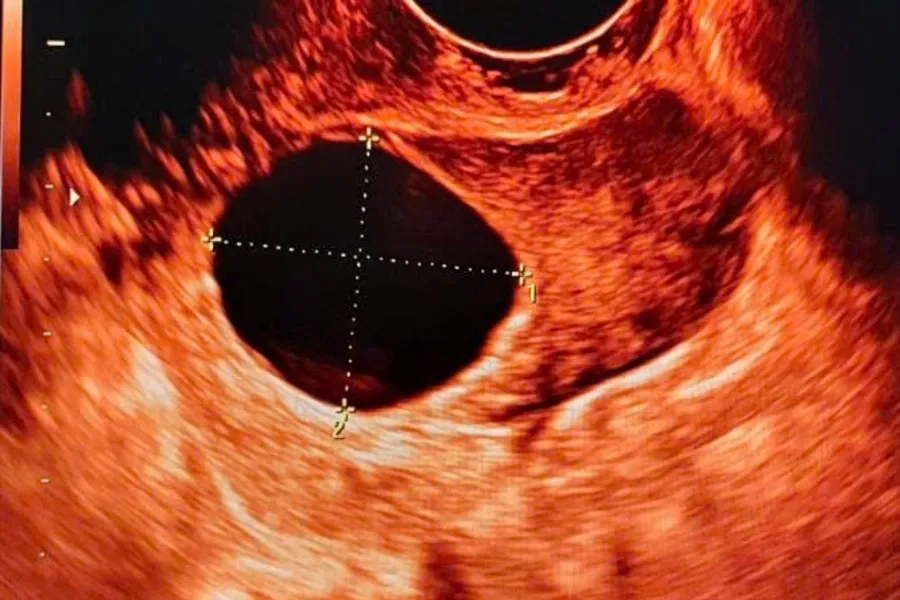

2. Bước 2: Kích thích buồng trứng

Bạn sẽ được chỉ định dùng thuốc kích thích buồng trứng nhằm tạo từ 1-2 nang trứng trưởng thành. Quá trình này thường bắt đầu từ ngày 2-3 của chu kỳ kinh và được theo dõi bằng siêu âm 2-3 lần để đánh giá sự phát triển nang trứng. Khi nang trứng đủ trưởng thành, bạn sẽ được tiêm thuốc để gây rụng trứng. Bơm tinh trùng thường thực hiện sau 36-38 giờ kể từ mũi tiêm cuối cùng.

Tiêm thuốc kích trứng giúp nang trứng phát triển

3. Chất lượng nang noãn và tình trạng tử cung

Hiệu quả IUI phụ thuộc nhiều vào tình trạng tử cung và chất lượng nang trứng. Nội mạc tử cung cần đủ tốt và từ 1-2 nang trứng đạt tiêu chuẩn về kích thước vào ngày kích thích rụng trứng. Với phụ nữ mắc lạc nội mạc tử cung nặng, tổn thương ống dẫn trứng hoặc tinh trùng bất thường nặng có thể làm giảm hiệu quả của IUI, khi đó IVF thường là lựa chọn ưu tiên.

Chất lượng nang noãn là yếu tố quan trọng hỗ trợ tăng cơ hội thụ thai